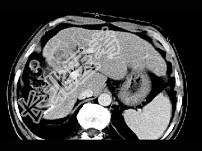

- 单项选择题女性,56岁, 腹胀、双下肢水肿、乏力、食欲不振,影像所见如下图, 最佳的诊断是  (    )

- A、酒精性肝硬化并肝血管瘤

- B、血吸虫肝硬化并肝癌

- C、肝炎后肝硬化并肝癌

- D、局限性脂肪肝

- E、原发性肝癌